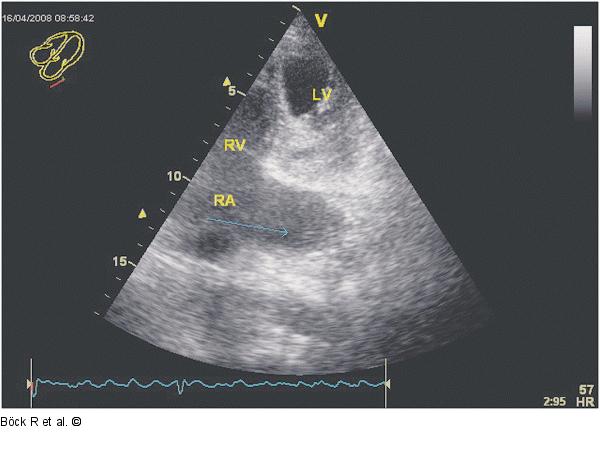

Abbildung 7: Sinus coronarius Kaudal angulierter modifizierter Vierkammerblick nach Kontrastmittelgabe (Pfeil zum coronarius) |

Kaudal angulierter modifizierter Vierkammerblick nach Kontrastmittelgabe (Pfeil zum coronarius) |